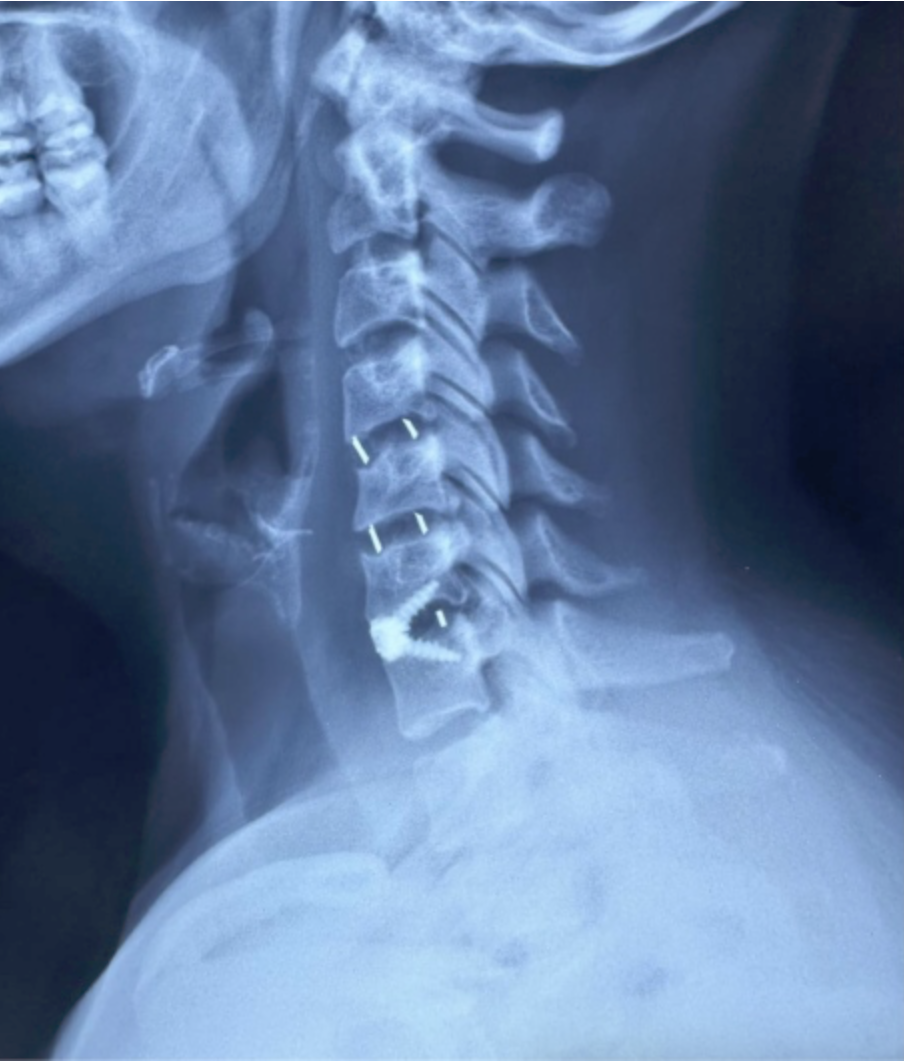

SURGERIES

RESULTS